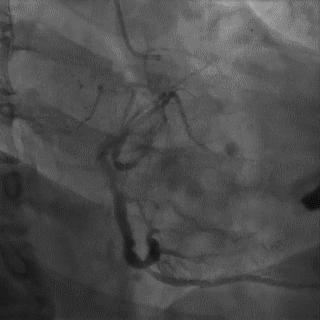

食管后起源右锁骨下动脉是一种较为少见的变异类型,发生率约为0.5%,食管后起源右锁骨下动脉是在右颈总动脉、左颈总动脉和左锁骨下动脉发出后直接起源于主动脉,随后绕行于食管的后方(图4)。由于食管后起源右锁骨下动脉进入主动脉的位置过于靠后,因此操作导引钢丝时非常容易进入降主动脉,此时前送造影导管至右锁骨动脉在主动脉的入口部,通过逆时针旋转导管使导管尖端指向升主动脉方向后再前送导丝。但即使应用上述方法也很难使导丝到位,大多数情况下不得不更换为对侧桡动脉或股动脉路径。

图4 食管后起源右锁骨下动脉

图5 食管后起源右锁骨下动脉造影导管到位处理:先尝试常用方法,包括选用亲水涂层导丝、前送导丝时患者深吸气以拉直血管、利用造影导管的头端弯曲调整导丝的尖端走向、利用导管和导丝的相对运动前送导丝等等,努力将导丝送入升主动脉